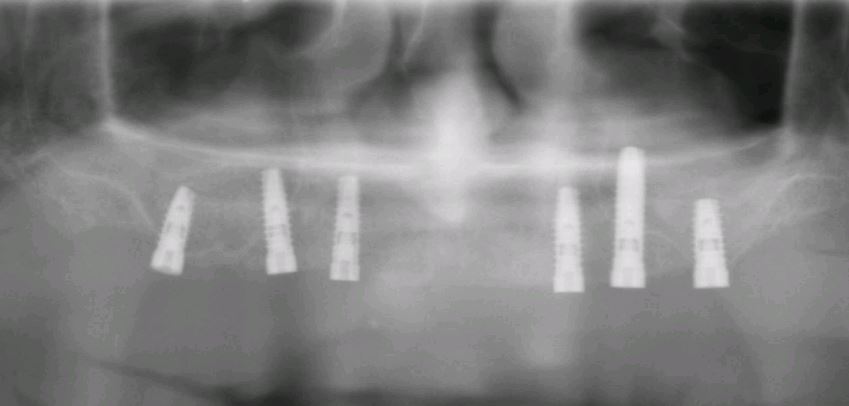

Sind nun alle Zähne des Kiefers verloren gegangen oder ist es notwendig alle restlichen Zähne zu entfernen, bleibt den Patienten normalerweise nichts anderes als eine konventionelle Vollprothese. Hier kann durch das spezielle Verfahren des Einbrigens von vier Implantaten ein Zahnersatz bereits in sehr zügiger Weise im Mund befestigt werden. Diese Methode ist an bestimmte Vorgaben gebunden und nicht immer ohne weiteres anwendbar. Bei günstigen Bedingungen kann es sogar möglich sein sogenannte "feste Zähne an einem Tag" zu bekommen.

All-on-4-Behandlungskonzept